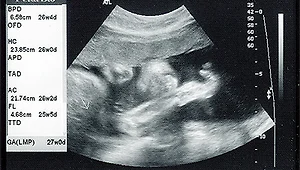

2003년 9월 2일 임신 26주째 2003년 9월 2일 임신 26주째 사진입니다. 2003. 12. 5.